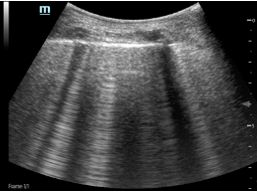

Image C1 is a real-time scan of a normal lung with POCUS.

Figure C2 is a CT scan of a patient who had a collection of some fluid in the chest.